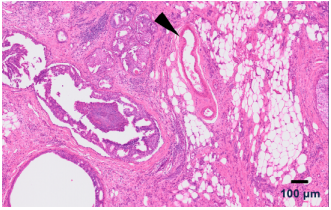

这份 FFPE 人类乳腺导管原位癌样本的 Visium HD 分析构建了 一张无偏的全转录组图谱,并鉴定出肿瘤微环境中的主要 细胞类型和状态。

▲自信地绘制血管等小型生物结构中细胞类型的空间排布。

Visium HD 数据是以 2 µm 以及多种拼接尺寸输出的。上图中的数据是在 8 µm 下可视化的。